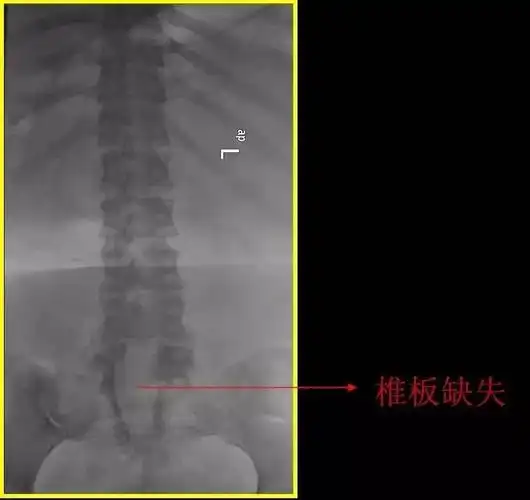

隐形脊柱裂的腰骶椎隐裂生理病理表现

温故知新脊柱裂的分型